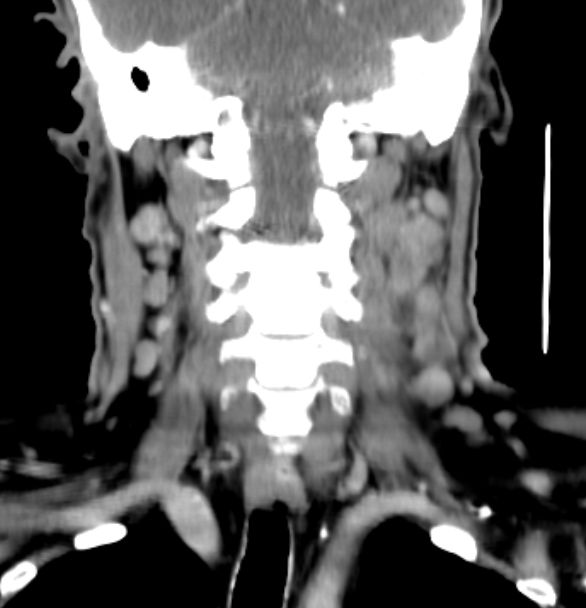

64-jähriger Mann mit tumoröser Raumforderung der linken Tonsille. Die primäre Histologie war verdächtig auf ein entdifferenziertes p16-positives Plattenepithelkarzinom. Bei der Radikaloperation wurden 84 Lymphknoten der Level 2-4 beiderseits entfernt, von denen 55 metastatisch befallenen waren. Zusätzlich wurde ein nicht zugänglicher Lymphknoten unterhalb der Karina festgestellt. Die transösophageale Punktion dieses Lymphknotens ergab den Verdacht eines malignen Lymphoms. Daraufhin wurden von den zervikalen Lymphnoten zusätzliche immunhistochemische Untersuchungen durchgeführt. Nach Vorliegen der Referenzpathologie handelt es sich um den seltenen Fall eines sarkomatoiden Lymphom oder eines histiozytischen Sarkoms. Diese Zellen sehen einem entdifferenzierten Plattenepithelkarzinom sehr ähnlich. | ||

Zahlreiche vergrößerte zervikale Lymphknoten.![]() |